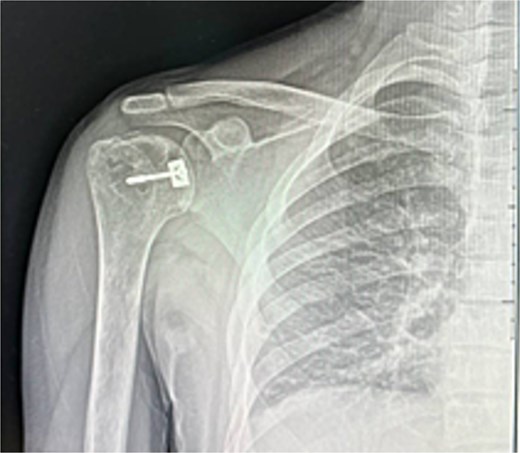

At 2 weeks, the wound healed well, and rehabilitation began at 4 weeks. At 6 weeks, he achieved 120° forward flexion, 160° abduction, and improved external rotation. At 2 months, flexion increased to 140°, abduction to 170°. By 6 months, he reached 160° flexion, 170° abduction, with minimal external/internal rotation lag (Figs 4–6).